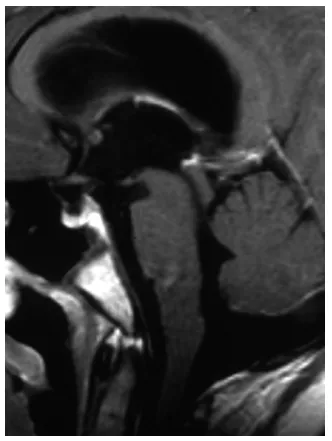

命运总爱开残忍的玩笑。就在入院当天,昭昭突然昏迷过去。急诊MRI显示,那个带蒂的肿瘤像瓶塞一样完全掉进了导水管(图2),造成了梗阻。医生面色凝重地说:“必须立即手术。”

图2.患者昏迷后急诊矢状位T2加权MRI,可见带蒂肿瘤深部移位至导水管内,造成完全性梗阻。